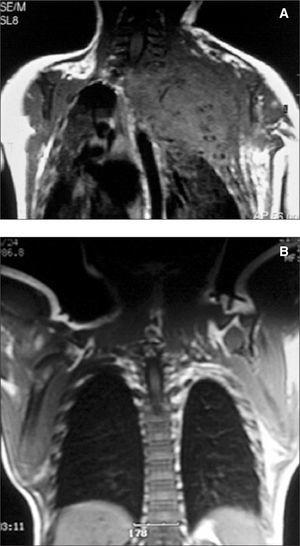

Caso 1

Paciente de pocas horas de vida con gran tumoración vascular que afectaba a tórax y abdomen (fig. 1) y que desarrolló una grave coagulopatía (4.000 plaquetas/μl) con hemotórax y hemorragia digestiva así como insuficiencia cardíaca congestiva que no respondían a tratamiento farmacológico y que provocaron el fallecimiento del recién nacido a las 8 h de vida. La necropsia puso de manifiesto alteraciones histológicas compatibles con hemangioendotelioma kaposiforme con afectación de tórax y abdomen.

Figura 1.Caso 1.